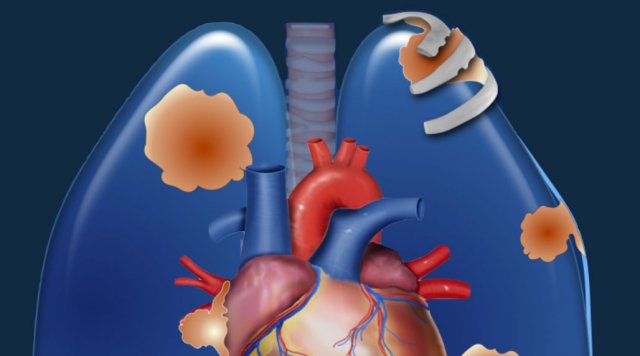

Pulmonary Hypertension and Thromboembolic disease

Pulmonary Hypertension